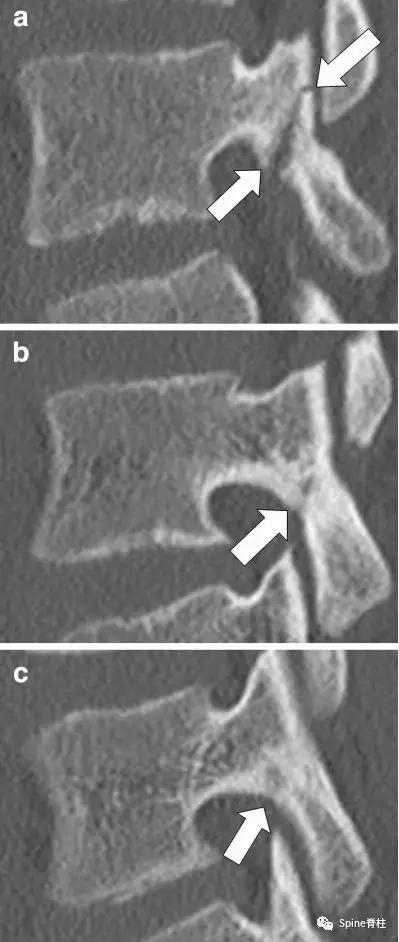

- 峡部裂的Morita分型

- 早期峡部裂( early):可见峡部骨折线

- 进展期峡部裂 (progressive):骨折断端间隙增宽

- 终末期峡部裂 (terminal): 假关节形成

图:早期(a),进展期(b),终末期(c)

随后,Sairyo教授进一步CT研究,将Morita分型早期又分为 最早期 (very early): 骨折线模糊或不连续的骨折线和 晚早期 (late-early): 骨折线清晰明显。

图:腰5双侧峡部裂,右侧为 最早期 ,左侧为 晚早期